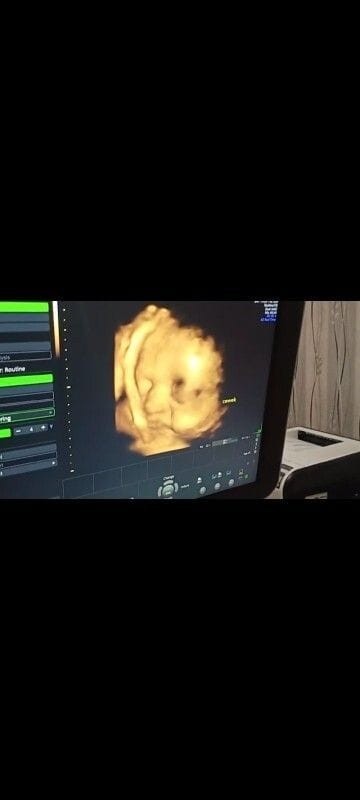

Kmrin wktu usg si ade senyum² aja.. sehat² slalu nak..❤️ 34W3D

Degdegan nunggu gerakan debaynya🥰 degdegan sma hasil usg jnis kelaminnya